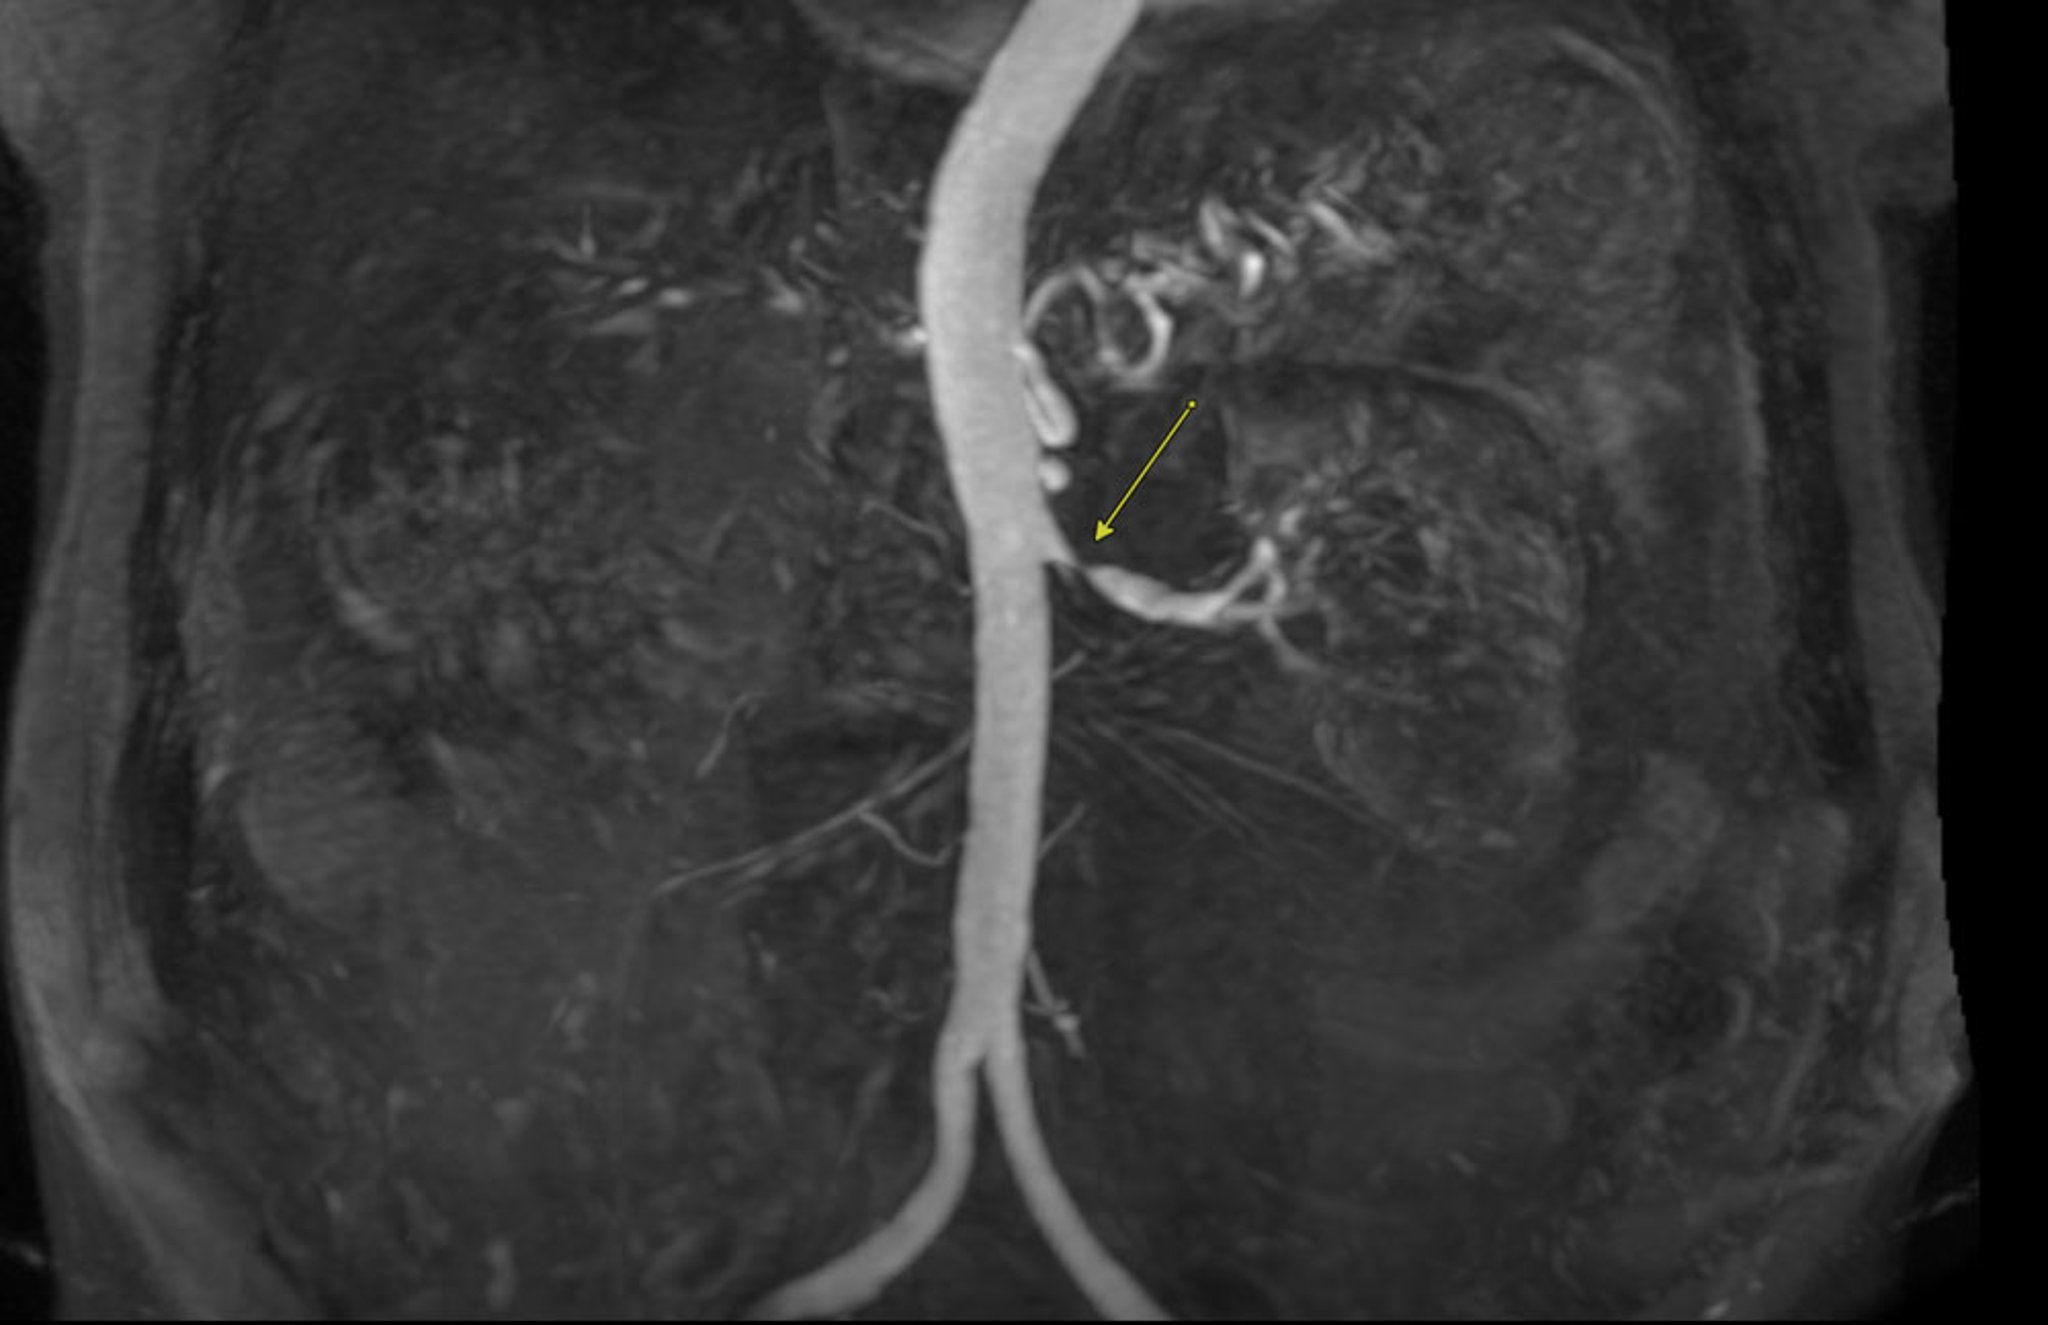

• Magnetic resonance angiography (MRA): MRA may be done without contrast or with gadolinium-based contrast. It is used to evaluate vascular size and/or stenosis severity without exposing the patient to ionizing radiation. However, this technique has suboptimal spatial resolution for visualizing small, mobile vascular beds.